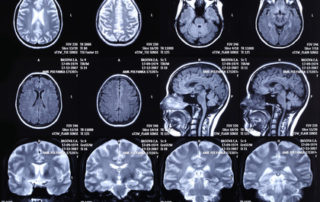

On connaissait l’influence du stress sur les problèmes d’addiction. Des chercheurs en neurosciences ont aujourd’hui découvert par quels mécanismes dans le cerveau le stress poussait à l’augmentation de la consommation d’alcool. Un nouvel espoir dans le traitement des dépendances. Les rongeurs stressés consomment plus d'alcool Une équipe de chercheurs de l’Université de Pennsylvanie aux Etats-Unis [...]